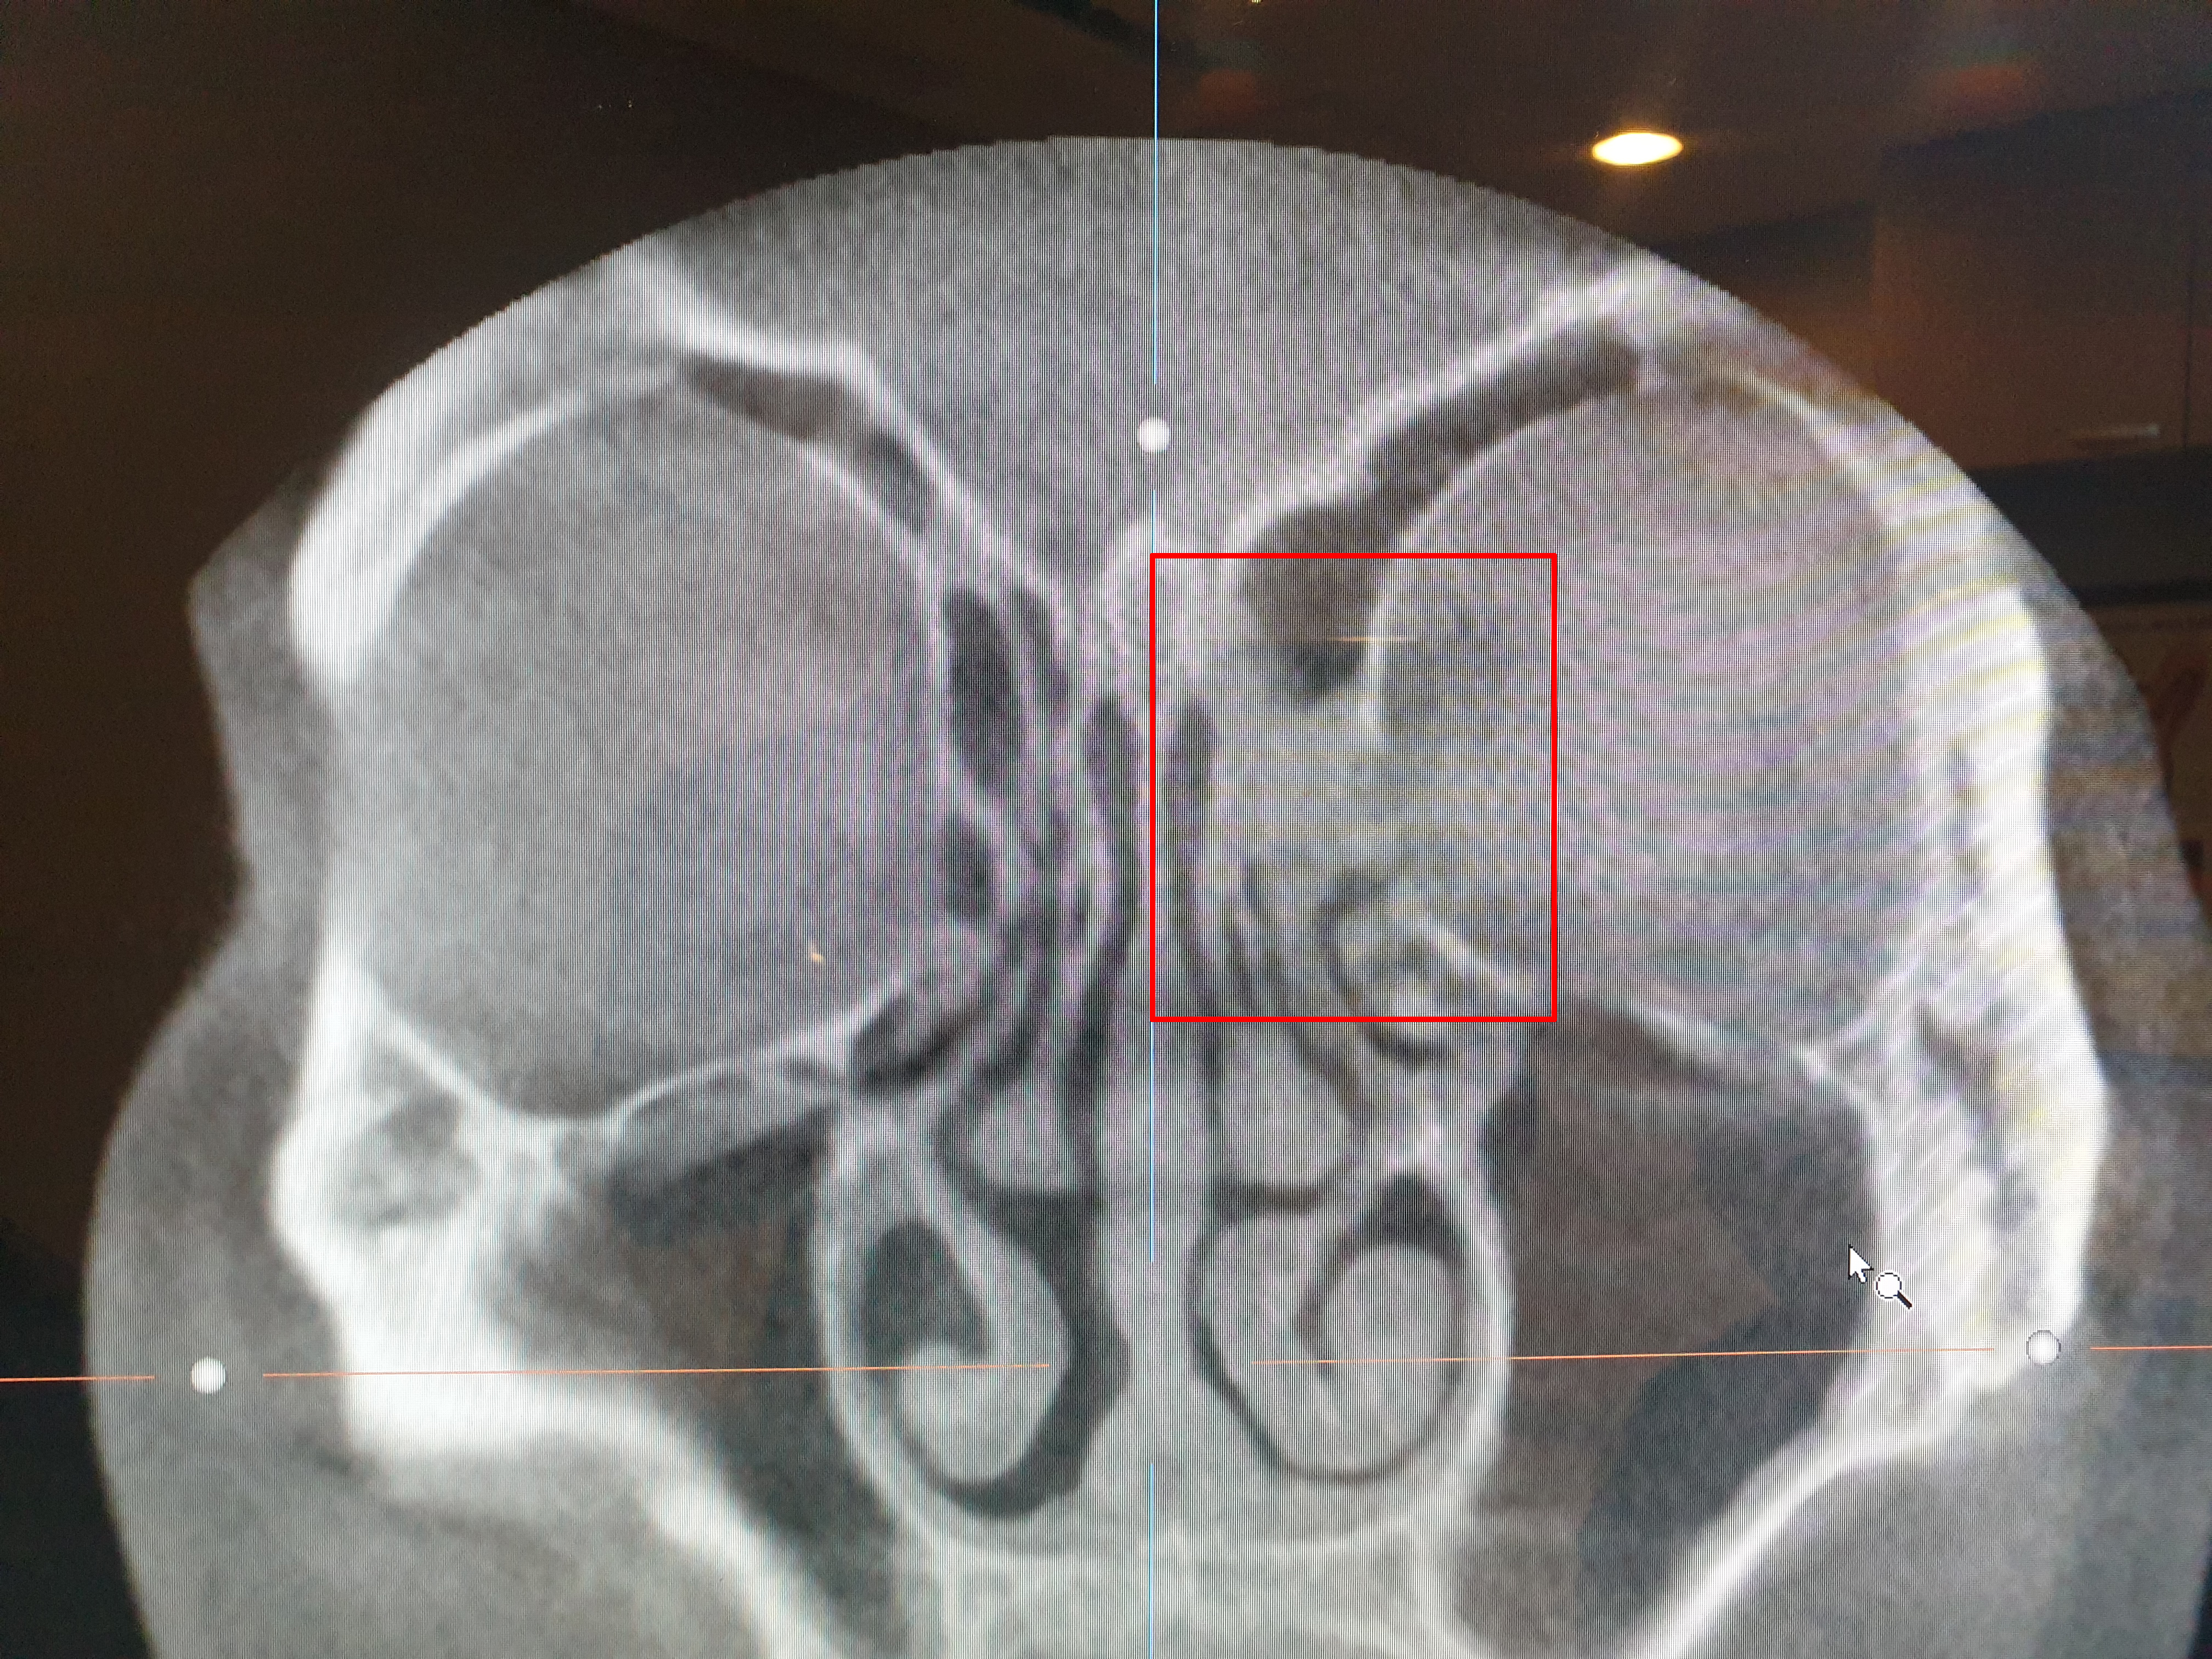

오른쪽 빨간 네모칸을 보면

왼쪽과는 다르게 막혀 있는 것을 볼 수 있다.

의사 선생님 말로는

염증으로 점막이 부어서 막혀 있는 것 같다고 하셨다.